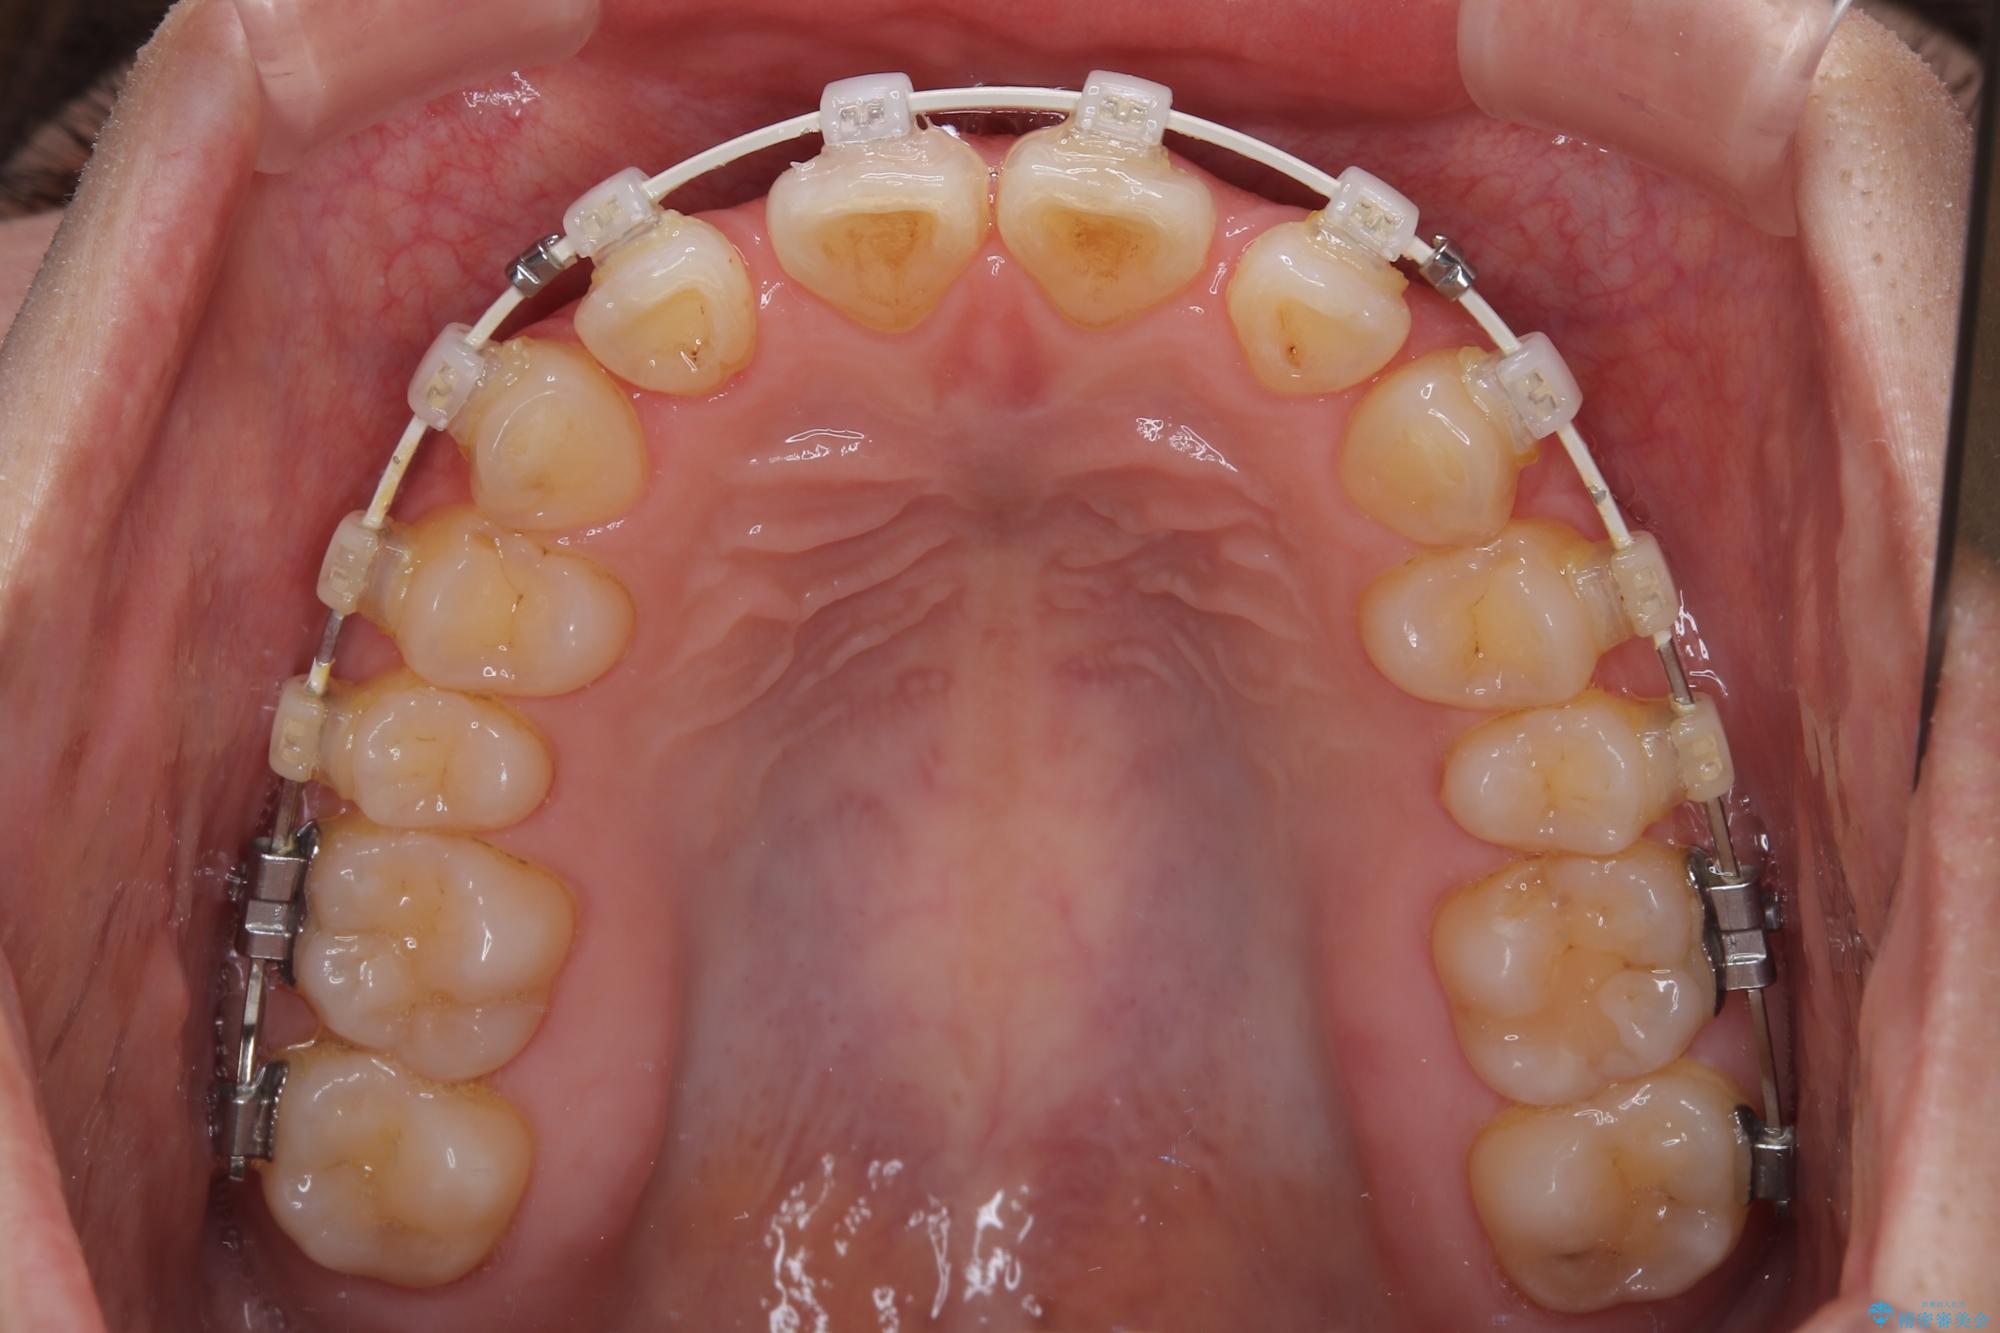

- 審美装置

下顎臼歯を起き上がらせるためにユーティリティーアーチを使用し、一気に深い咬み合わせを改善することができました。